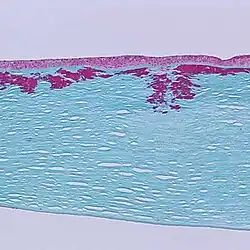

Reis-Bücklers corneal dystrophy. Light microscopy of cornea showing characteristic red stained deposits of mutated transforming growth factor beta-induced protein in the superficial corneal stroma. Masson's trichrome stain.